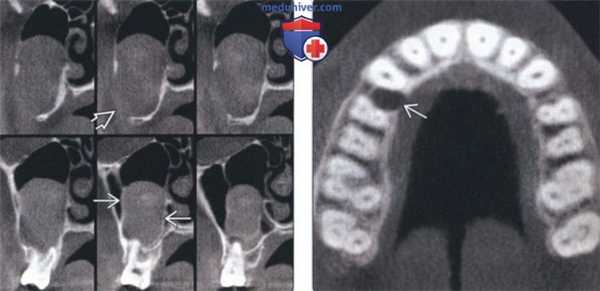

о МРТ: Т2-ВИ с подавлением сигнала от жира и постконтрастные Т1-ВИ для диагностики КОО челюсти, периневрального распространения БКК(а) МРТ, постконтрастное Т1-ВИ, режим подавления сигнала от жира: у шестилетнего ребенка с диагностированным СБКН в переднем левом альвеолярном отростке верхней челюсти визуализируется небольшое кистозное объемное образование, характерное для кератоцистной одонтогенной опухоли. Определяется слабое периферийное контрастирование кисты по типу тонкого ободка. В медиальных отделах кисты виден непрорезавшийся зуб. МРТ была проведена в качестве скринингового обследования для диагностики медуллобластомы.

(б) МРТ, Т2-ВИ, режим подавления сигнала от жира, аксиальный срез: у того же пациента визуализируются умеренное повышение сигнала от содержимого кисты, а также гипоинтенсивный непрорезавшийся зуб, расположенный медиальнее. (а) МРТ, Т2-ВИ, режим подавления сигнала от жира, коро-нальный срез: в левой носовой полости визуализируется гипоинтенсивное на Т2-ВИ объемное образование, заполняющее ее и прорастающее в ячейки решетчатой кости. Этому пациенту 19 лет с СБКН был проведен курс лучевой терапии медуллобластомы, в результате чего возникала радио-индуцированная рабдомиосаркома.

(Слева) На корональныхсрезах (КЛКТ) задних отделов основания черепа у пациента с СБКН в области третьего моляра определяется образование, напоминающее кисту, распространяющееся в верхнечелюстную пазуху. Кортикальная пластинка на периферии означает, что образование возникло за пределами пазухи. Латеральная стенка верхнечелюстной пазухи перфорирована.

(Справа) На аксиальной КЛКТ у этого же пациента определяется маленький формирующийся очаг в верхней челюсти справа. Этот очаг, выявленный случайно, свидетельствует о том, насколько важен анализ данных с целью поиска дополнительных поражений.1. Общая характеристика: